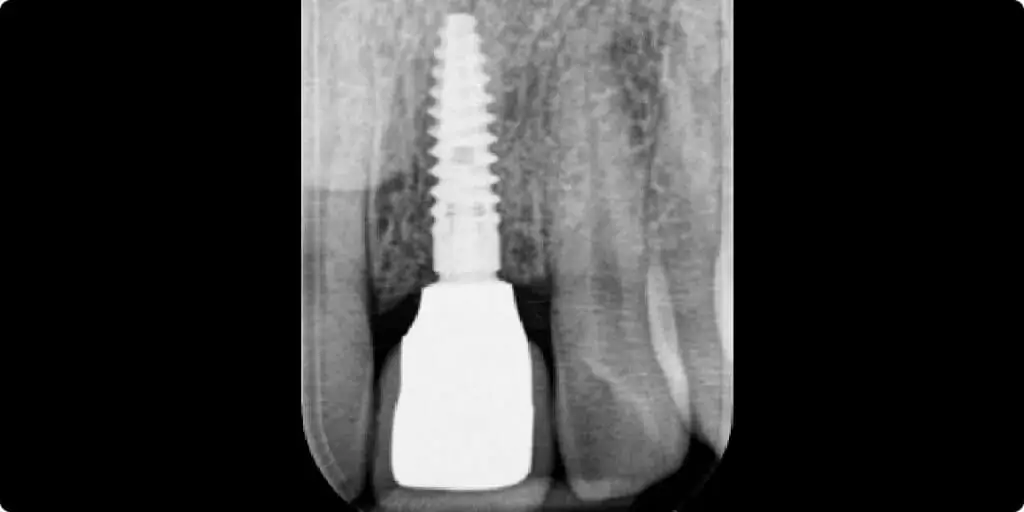

Implantat med tandkrone

Billederne og røntgen viser det færdige implantat med tandkrone.